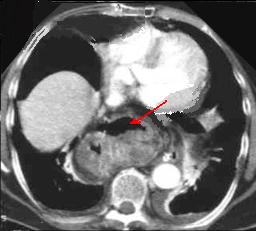

Hernie hiatale de type

I en coupe axiale TDM , fenetre mediastinale .

La poche hydro-aerique gastrique glisse alongee au

dessus hiatus oesophagien en arriere aureillete

gauche et ventricule gauche . |

Quelque images en TDM axiale de

hernie hiatale de type II et Type IV :